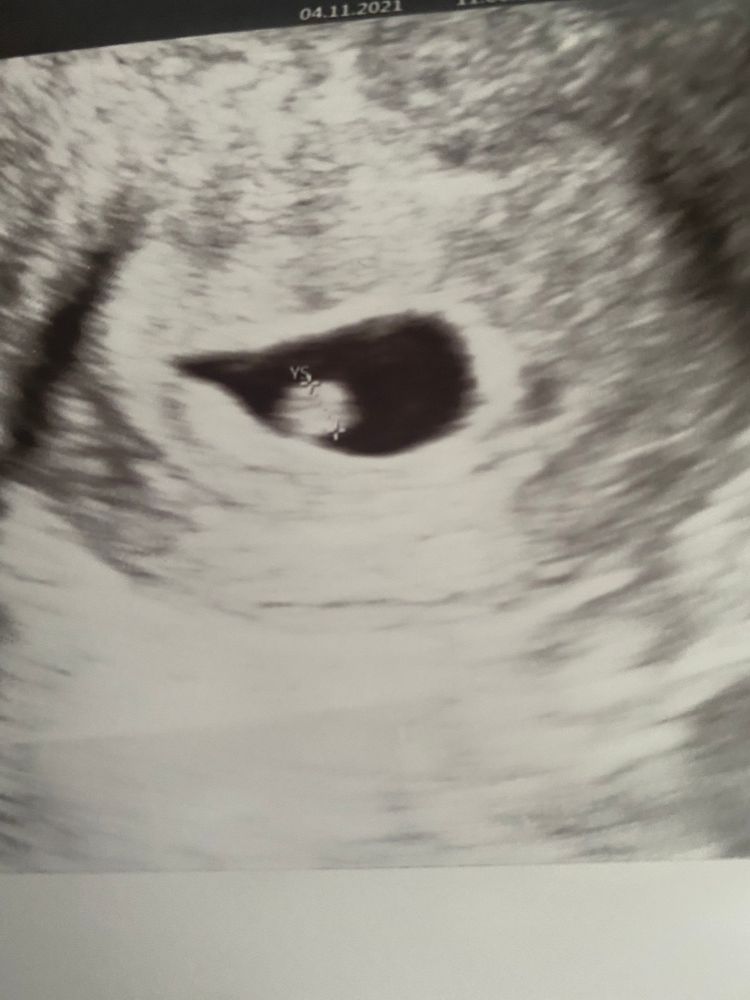

Юлия, вот, по этому первому узи методом рамзи должен быть мальчик Изображение